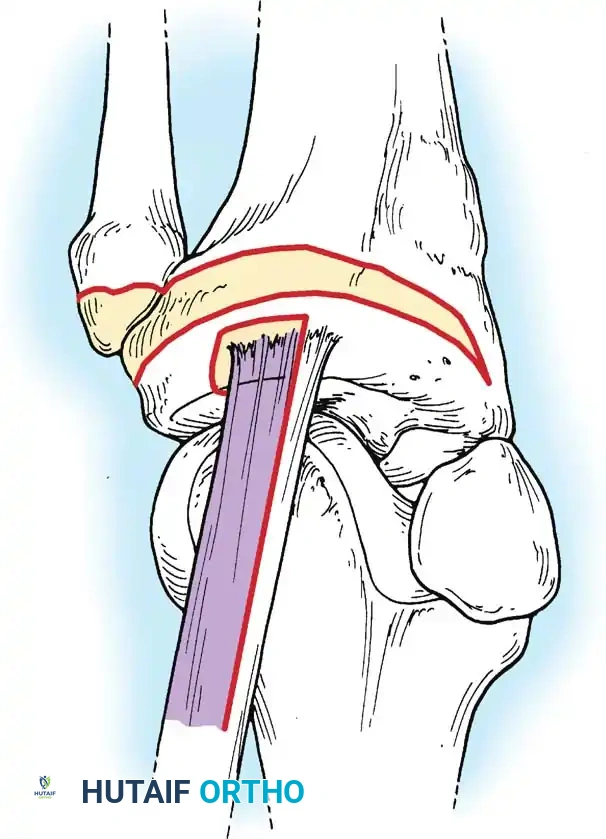

Image

The deep fascia is incised, and the sartorius fascia is identified. The superficial MCL is exposed. If the injury is an avulsion from the femoral origin or tibial insertion, it is repaired using heavy non-absorbable sutures and suture anchors.

Mid-substance tears are meticulously re-approximated. The deep capsular ligaments (meniscofemoral and meniscotibial) must be inspected. If the medial meniscus is peripherally detached, it is repaired to the capsule prior to tensioning the superficial MCL.